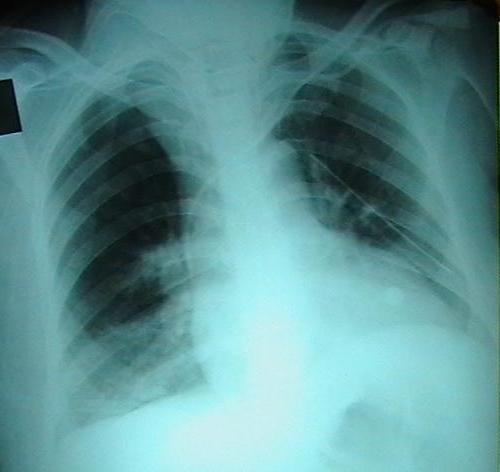

We present a-39-year old, Caucasian patient, developing severe hypoxia fallowing cesarean section under general anesthesia. The findings of the patient were diffuse subcutaneous emphysema; together with pneumothorax and pneumomediastinum TEF was diagnosed in the patient by bronchoscopy and eusophagoscopy performed due to cough and difficulty in swallowing developing after extubation.

我们接诊了一名39岁的白种人患者,该患者在全身麻醉下剖宫产术后出现严重缺氧。患者的检查结果为弥漫性皮下气肿;同时伴有气胸和纵隔气肿,由于拔管后出现咳嗽和吞咽困难,通过支气管镜检查和食管镜检查诊断患者患有气管食管瘘。